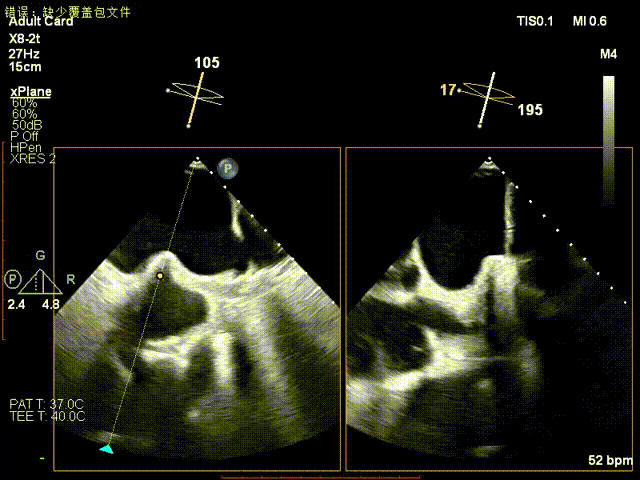

术前食道超声示二尖瓣重度关闭不全,重度反流;

术前食道超声

食道超声引导下房间隔穿刺;

超声引导房间隔穿刺